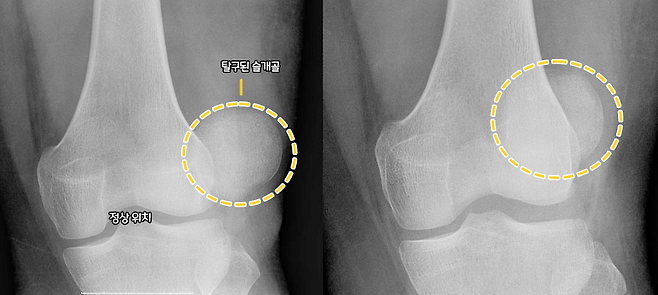

슬개골은 무릎을 덮고 있는 작은 뼈로 무릎의 움직임을 도와주는 역할을 하는데요. 이 슬개골이 원래 위치에서 자꾸 벗어나는 현상을 '슬개골 탈구'라고 합니다.

슬개골 탈구가 생기면 강아지가 절뚝거리고 무릎에서 뚝뚝 소리가 나는 등의 증상을 보이게 되는데요. 걷는 게 전보다 힘들고 통증도 있어 강아지 일상생활에 불편함을 준답니다. 방치할 경우 관절염이나 십자인대 파열로 이어질 수 있어 잘 관리해 주어야 한답니다.